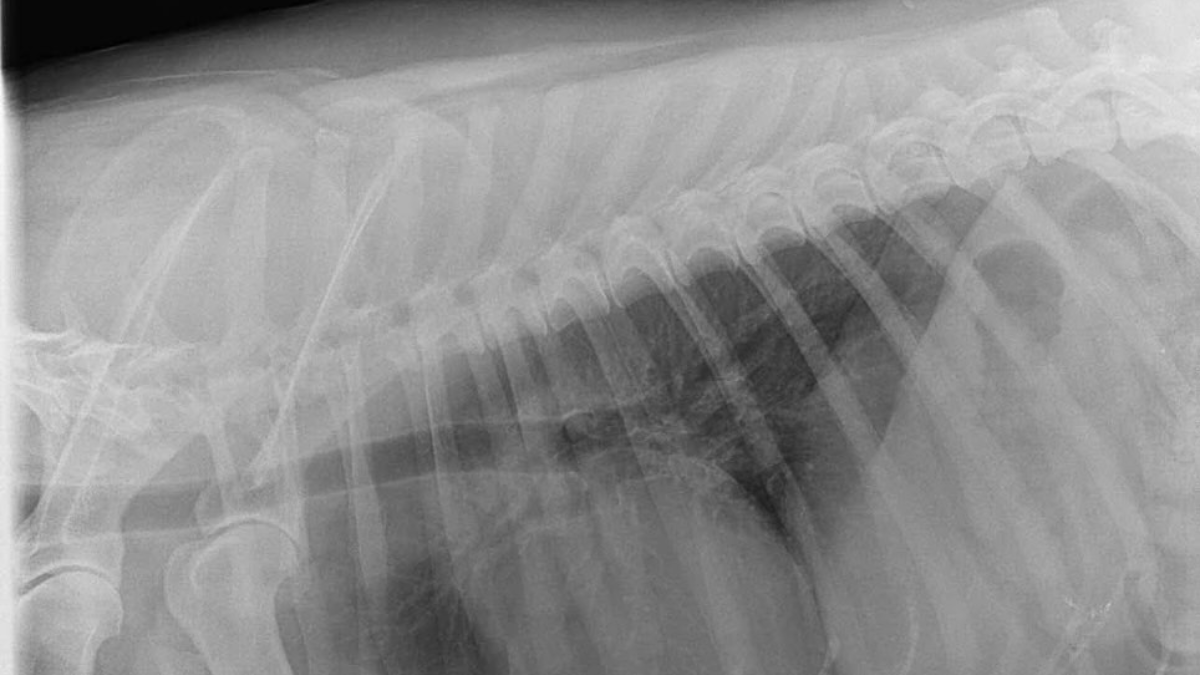

У притулку “Дім Сірка” повідомили, що пес Джек пережив складну і болісну операцію. Його вдалося врятувати завдяки тривалому процесу обстеження, аналізів, ехокардіографії серця та рентгену. Операція була необхідною, аби дати йому шанс на життя без болю.